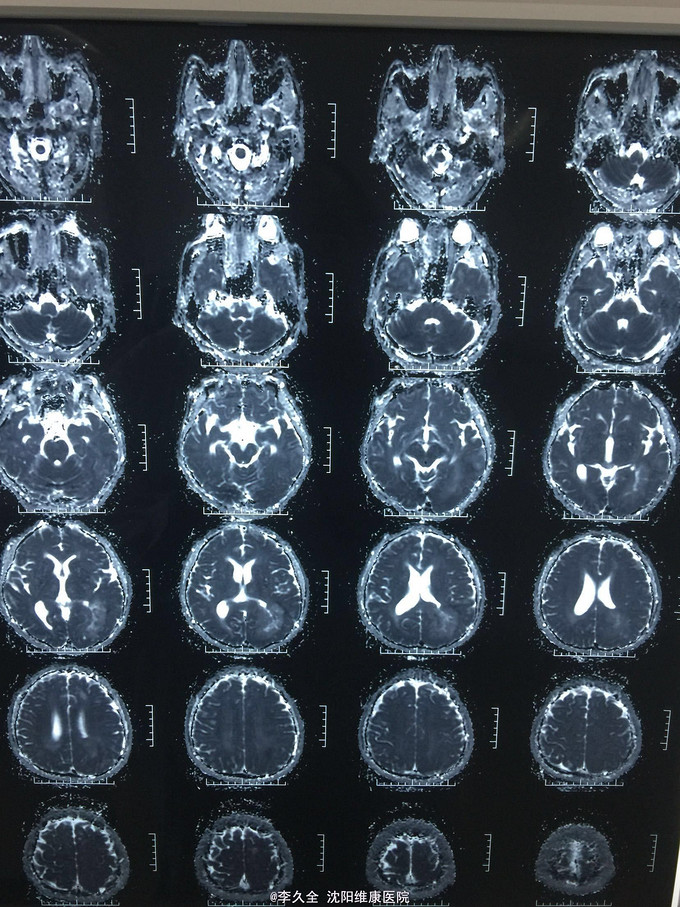

男,62岁,以头晕、视野缺损、记忆力减退、失写、失算7个月入院! 现病史:去年7月出现头晕,就诊于医院,行头CT:代诉未见异常,口服药物无效,后出现右侧视野缺损,走路撞墙、撞门,就诊于当地医院、北京协和医院,考虑“㬵质瘤”,近3个月出现近事遗忘为主,平时写字不会,计算力下降,不认识人! 既往史:2型糖尿病5年!

查体:BP:150/80mmHg,心肺腹无异常。神清,不能言语,失写、失算、失认,双曈孔等大正圆,直径3.0mm,光敏,四肢能够活动,右侧肌张力增高,巴氏征R+L-,颈强3横指,克氏征阳性! 影像MR:

1.颅内占位,胶母可能大! 2.2型糖尿病